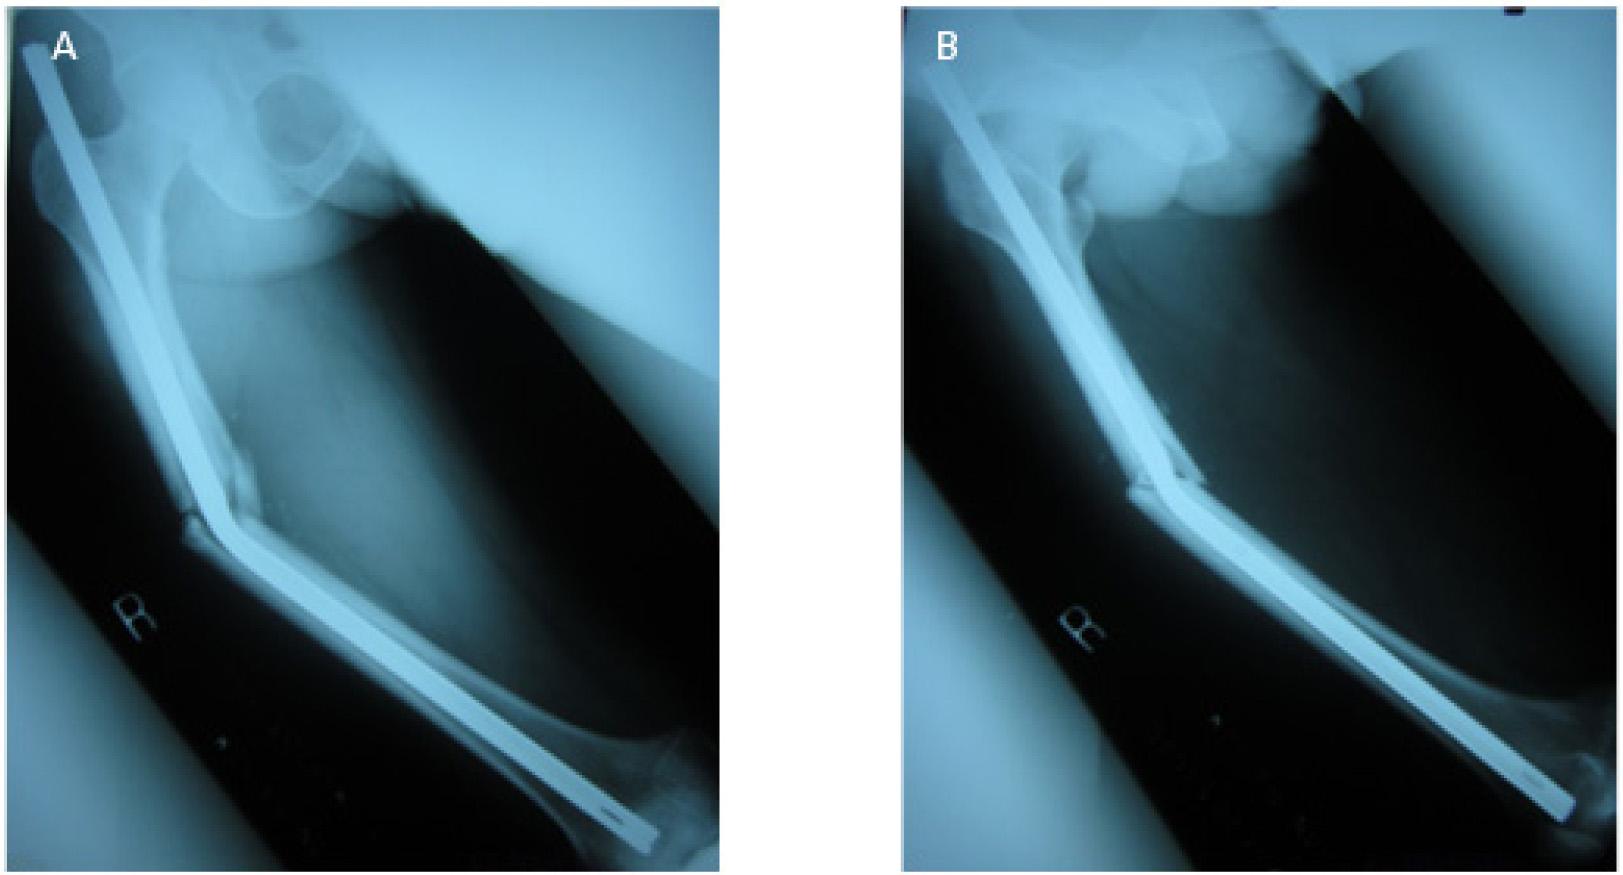

Figure 2